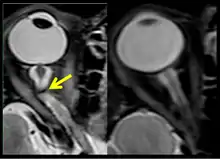

The sixth case of visual changes of an ISS astronaut was reported after return to Earth from a 6-month mission. When he noticed that his far vision was clearer through his reading glasses. A fundus examination performed 3 weeks postflight documented a grade 1 nasal optic-disc edema in the right eye only. There was no evidence of disc edema in the left eye or choroidal folds in either eye (Figure 13). MRI of the brain and eyes days postflight revealed bilateral flattening of the posterior globe, right greater than left, and a mildly distended right optic nerve sheath. There was also evidence of optic-disc edema in the right eye. A fundus examination postflight revealed a "new onset" cotton-wool spot in the left eye. This was not observed in the fundus photographs taken 3 weeks postflight.[5]

The seventh case of visual changes associated with spaceflight is significant in that it was eventually treated postflight. Approximately 2 months into the ISS mission, the astronaut reported a progressive decrease in his near and far acuity in both eyes. The ISS cabin pressure, CO2 and O2 levels were reported to be within normal operating limits and the astronaut was not exposed to any toxic substances. He never experienced losses in subjective best-corrected acuity, color vision or stereopsis. A fundus examination revealed a grade 1 bilateral optic-disc edema and choroidal folds (Figure 15).[5]